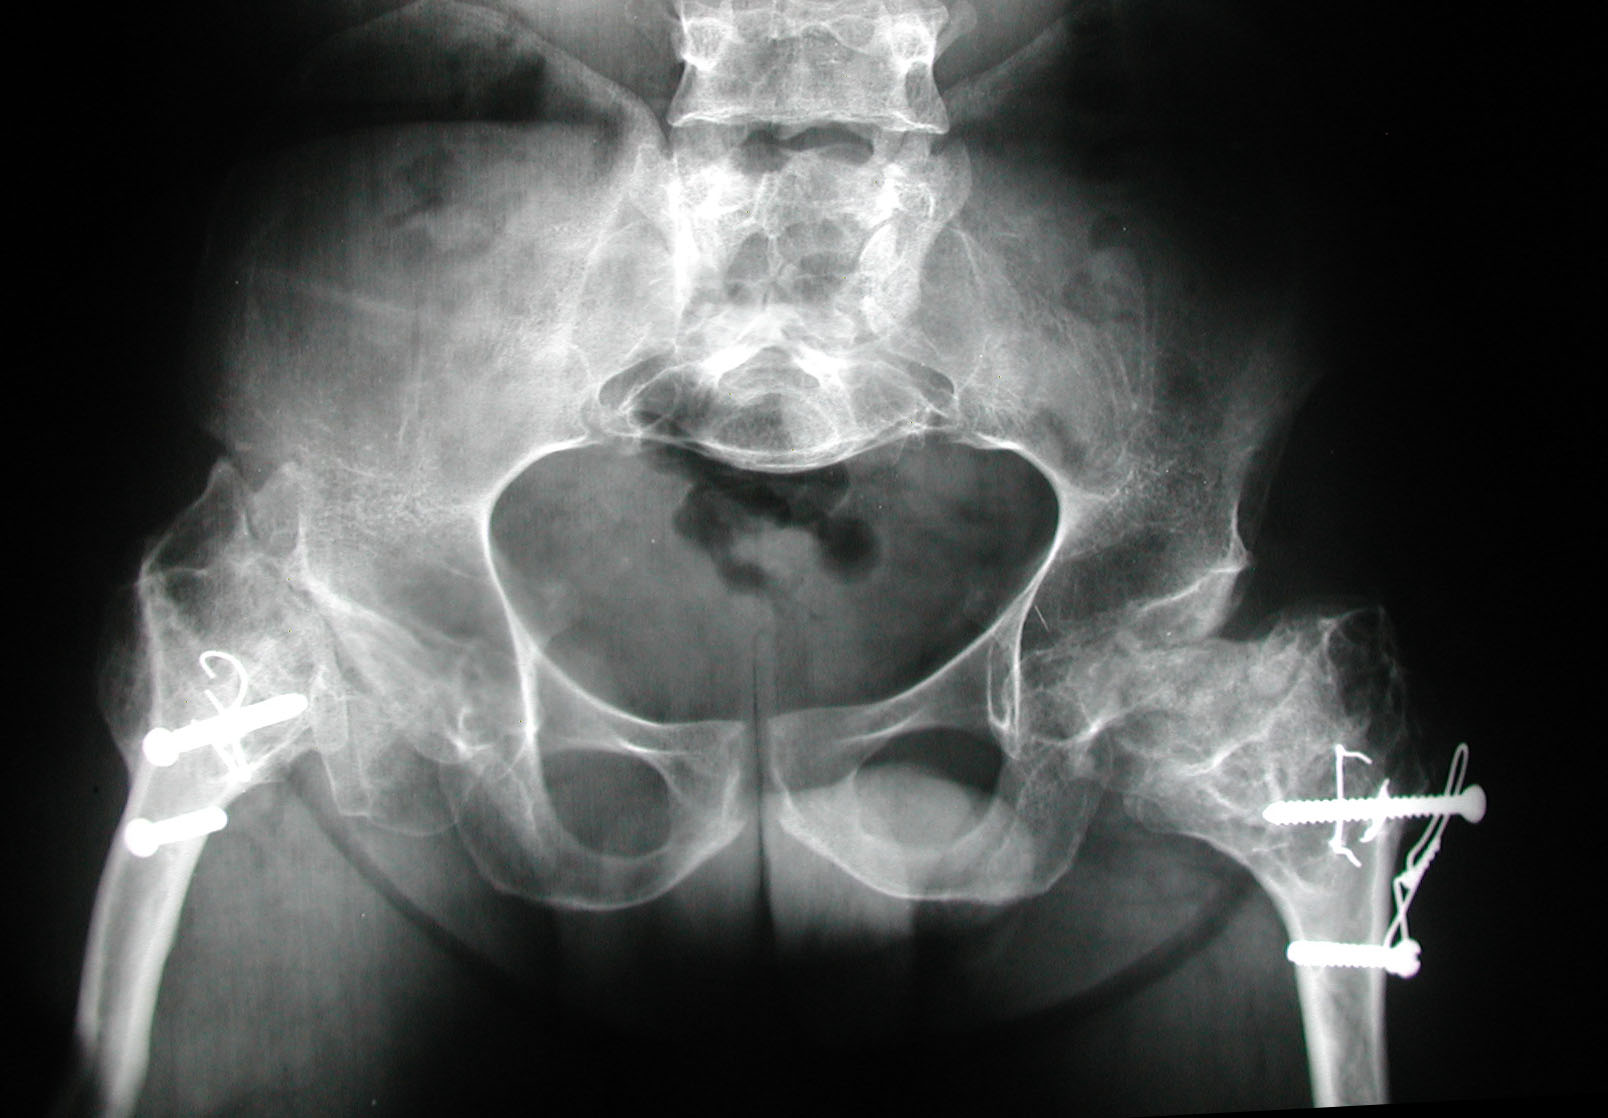

7. Sekundiak TD. Total hip arthroplasty in patients with dwarfism. Orthopedics 2005;28(9):1075-8.

8. Huo MH, Salvati EA, Liberman JR, Burstein AH, Wilson PD Jr. Custom-designed femoral prostheses in total hip arthroplasty

done with cement for severe dysplasia of the hip. J Bone Joint Surg Am 1993;75:1497-1504.

9. Osagie L, Figgie M, Bostrom M. Custom total hip arthroplasty in skeletal dysplasia. International Orthopedic 2012;36:527-1.

10. Chiavetta JB, Parvizi J, Shaughnessy WJ, Cabanela ME. Total hip arthroplasty in patients with dwarfism. J Bone Joint Surg

Am 2004;86:298-303.

11. Ain MC, Andres BM, Somel DS, Fishkin Z, Frassica FJ. Total hip arthroplasty in skeletal dysplasias. Patients selection,

preoperative planning, and operative techniques. J Arthroplasty 2004;19(1):1-7.